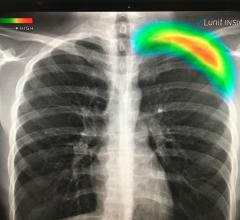

Featuring LANMIT (Large Area New-MIS Sensor and TFT) detector technology, the CXDI-50C DR system delivers diagnostic images with minimal X-ray exposure to patients. It also consists of a Canon Amorphous Silicon (a-Si) Flat Panel Detector and a Cesium Iodide (CsI) scintillator, allowing for effective X-ray absorption and high signal-to-noise performance.